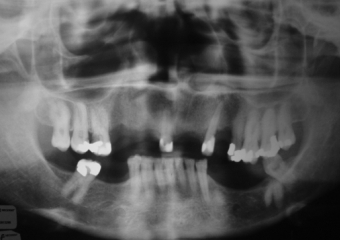

Rx Inicial